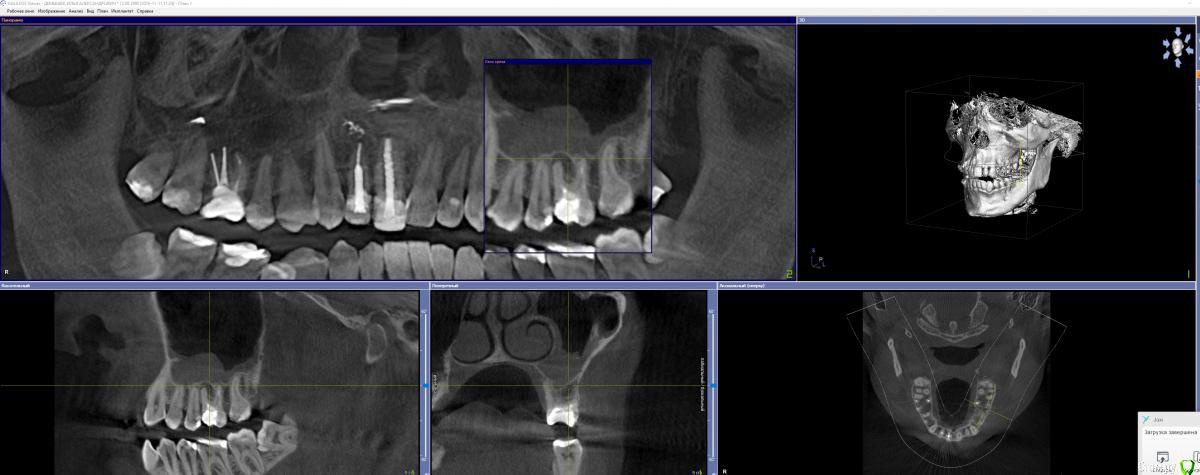

GoldJoker Опубликовано 3 декабря, 2017 Поделиться Опубликовано 3 декабря, 2017 Прошу совета знающих людей. Страдаю левосторонним гайморитом 5 лет, постоянные подтекания гноевидной слизи по задней стенке изредка выходящей через нос. На КТ 26 зуб киста, прикладываю 2 КТ с разницей в 1 год. Пролечли каналы под микраскопом, щечный канал был не пролечен ранее. Изначально зуб лечили 13 лет назад. Кистагранулема уменьшилась, проблема не ушла. Стоит ли ждать еще время либо нужно вырывать зуб, если вырывать. То будет ли сообщение посмотрите по снимку, если будет сообщение то чем его закрывать. И что с имплонтацией... Вообщем дайте совет что делать. КТ прикладываю. http://joxi.net/LmGp1LJueEWXb2- 2017 год фото http://joxi.net/82Q46k0Fj0XGKm- 2016 год фото https://yadi.sk/d/FB3RZAKD3QFND8- 2016 год полное кт 300мб. https://yadi.sk/d/rz8evJ5B3QFNDA- 2017 год полное кт 300мб. Ссылка на комментарий

Irouil Опубликовано 3 декабря, 2017 Поделиться Опубликовано 3 декабря, 2017 Я думаю, проблема в пазухе уже живёт отдельно от зуба. После перелечивания состояние сильно улучшилось, что в кости, так и в слизистой. Надо посмотреть как зуб реагирует на перкуссию (постукивания) и сравнить бы с тем, как он реагировал раньше. Создаётся впечатление, что повторное лечение оказалось успешным и зуб можно было бы не трогать, а прооперировать только саму пазуху. Если примете решение всё-таки удалять зуб, я бы подождал после этого два месяца, повторно снимок, если ситуация радикально не улучшается - эндоскопия пазухи, одномоментно синус лифт (по необходимости) и имплантация. Хотя тут возможны варианты. Сужу только по срезам, посмотреть всё КТ сейчас не могу. 1 Ссылка на комментарий

Irouil Опубликовано 7 декабря, 2017 Поделиться Опубликовано 7 декабря, 2017 (изменено) Все смешалось, кони, люди... Как-то Вы странно спрашиваете совета. Я бы Вас лечил так: 1) рекомендую досконально исследовать зуб, судя по срезам его лечение было успешным и удалять его поскорее я не советую (первичный очаг инфекции из зуба судя по всему изолирован качественной эндодонтией) 2) нужно оперировать пазуху, если соустье исправно (нужно кт, "нос дышит" не аргумент) - просто эндоскопически провести санацию. Доступ через нижний носовой ход или клыковую ямку (вероятнее второй вариант) 3) если удалите зуб и сформируется перфорация, способов закрыть соустье есть достаточно много, самый простой - щечным лоскутом (можно было бы закрыть только надкостницей - все бы закрывали, но пользуются обычно слизистыми или слизисто-надкостничными лоскутами). Под АБ защитой можно консервировать лунку (если есть шанс избежать синус лифта), а можно и не консервировать если все равно намечается синус лифт в будущем (этот вариант реальнее в Вашем случае). На имплантацию повлияет в первую очередь не тип лоскута (это решаемо) а костная поддержка мягких тканей 4) после удаления зуба ждите два месяца, дальше вилка: эндоскопия пазухи + синус лифт + имплантация или просто имплантация с/без синус лифтом/-а 5) Станислав Сысолятин спикер FESS дней у Андрея Лопатина от ЧЛХ, так что есть все шансы попасть к хорошему специалисту (если решитесь ехать к нему) Изменено 7 декабря, 2017 пользователем Irouil 1 Ссылка на комментарий

GoldJoker Опубликовано 24 декабря, 2017 Автор Поделиться Опубликовано 24 декабря, 2017 Все смешалось, кони, люди... Как-то Вы странно спрашиваете совета. Я бы Вас лечил так: 1) рекомендую досконально исследовать зуб, судя по срезам его лечение было успешным и удалять его поскорее я не советую (первичный очаг инфекции из зуба судя по всему изолирован качественной эндодонтией) 2) нужно оперировать пазуху, если соустье исправно (нужно кт, "нос дышит" не аргумент) - просто эндоскопически провести санацию. Доступ через нижний носовой ход или клыковую ямку (вероятнее второй вариант) 3) если удалите зуб и сформируется перфорация, способов закрыть соустье есть достаточно много, самый простой - щечным лоскутом (можно было бы закрыть только надкостницей - все бы закрывали, но пользуются обычно слизистыми или слизисто-надкостничными лоскутами). Под АБ защитой можно консервировать лунку (если есть шанс избежать синус лифта), а можно и не консервировать если все равно намечается синус лифт в будущем (этот вариант реальнее в Вашем случае). На имплантацию повлияет в первую очередь не тип лоскута (это решаемо) а костная поддержка мягких тканей 4) после удаления зуба ждите два месяца, дальше вилка: эндоскопия пазухи + синус лифт + имплантация или просто имплантация с/без синус лифтом/-а 5) Станислав Сысолятин спикер FESS дней у Андрея Лопатина от ЧЛХ, так что есть все шансы попасть к хорошему специалисту (если решитесь ехать к нему)Немного вывели материал в кость. Вокруг него небольшое потемнение. Правда что вокруг пломбировочного материала образуется фиброзная ткать. И это потемнение нужно считать ей а не оставшимся воспалением. Ссылка на комментарий